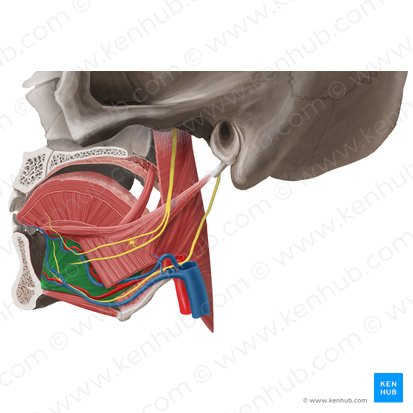

Genioglossus

Hyoglossus

Palatoglossus

Styloglossus